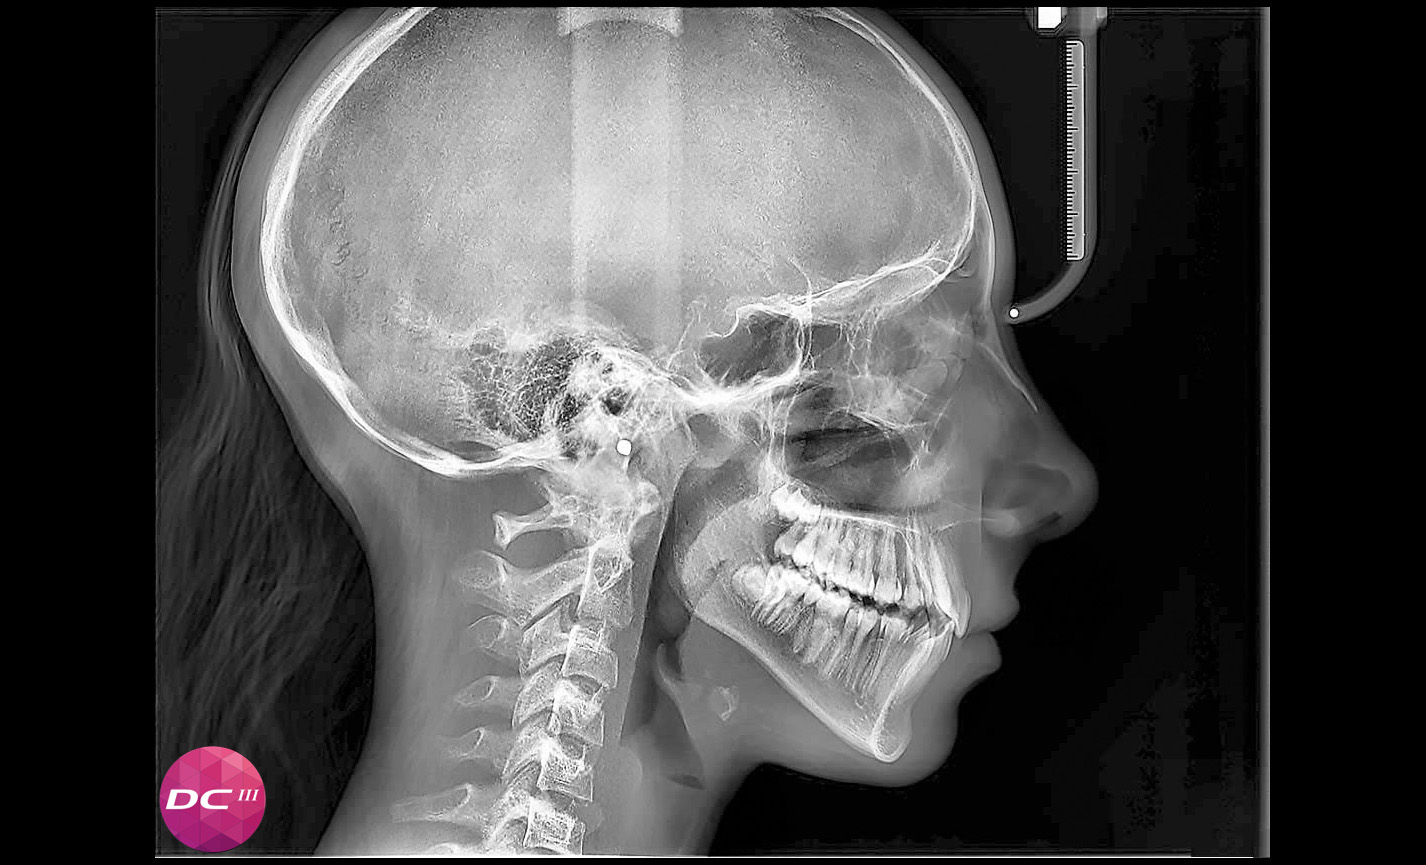

Téléradiographie

Latéro-latérale : avec détails des os et des tissus mous en évidence, fondamental pour les études céphalométriques.